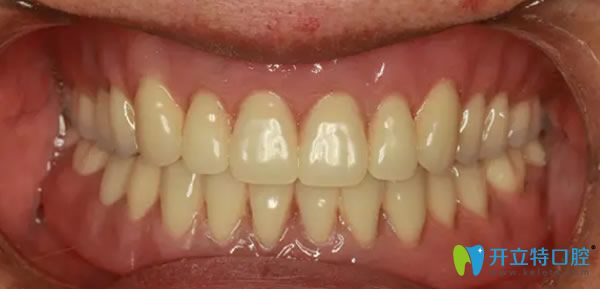

經(jīng)過6個(gè)月的恢復(fù)時(shí)間,來院復(fù)查,醫(yī)生說,牙槽骨和種植體緊密結(jié)合,可以為外婆裝上牙冠了,看來種植牙的成功率挺高的。術(shù)后外婆全口種植牙后的效果媲美真牙,整個(gè)人看起來也精神了好多,吃什么也更有胃口了,外婆激動(dòng)的說,擁有這一口美麗的大白牙,瞬間覺得我返老還童啦!哈哈!

全口牙缺失種植后的效果好不好?效果圖見證實(shí)力: